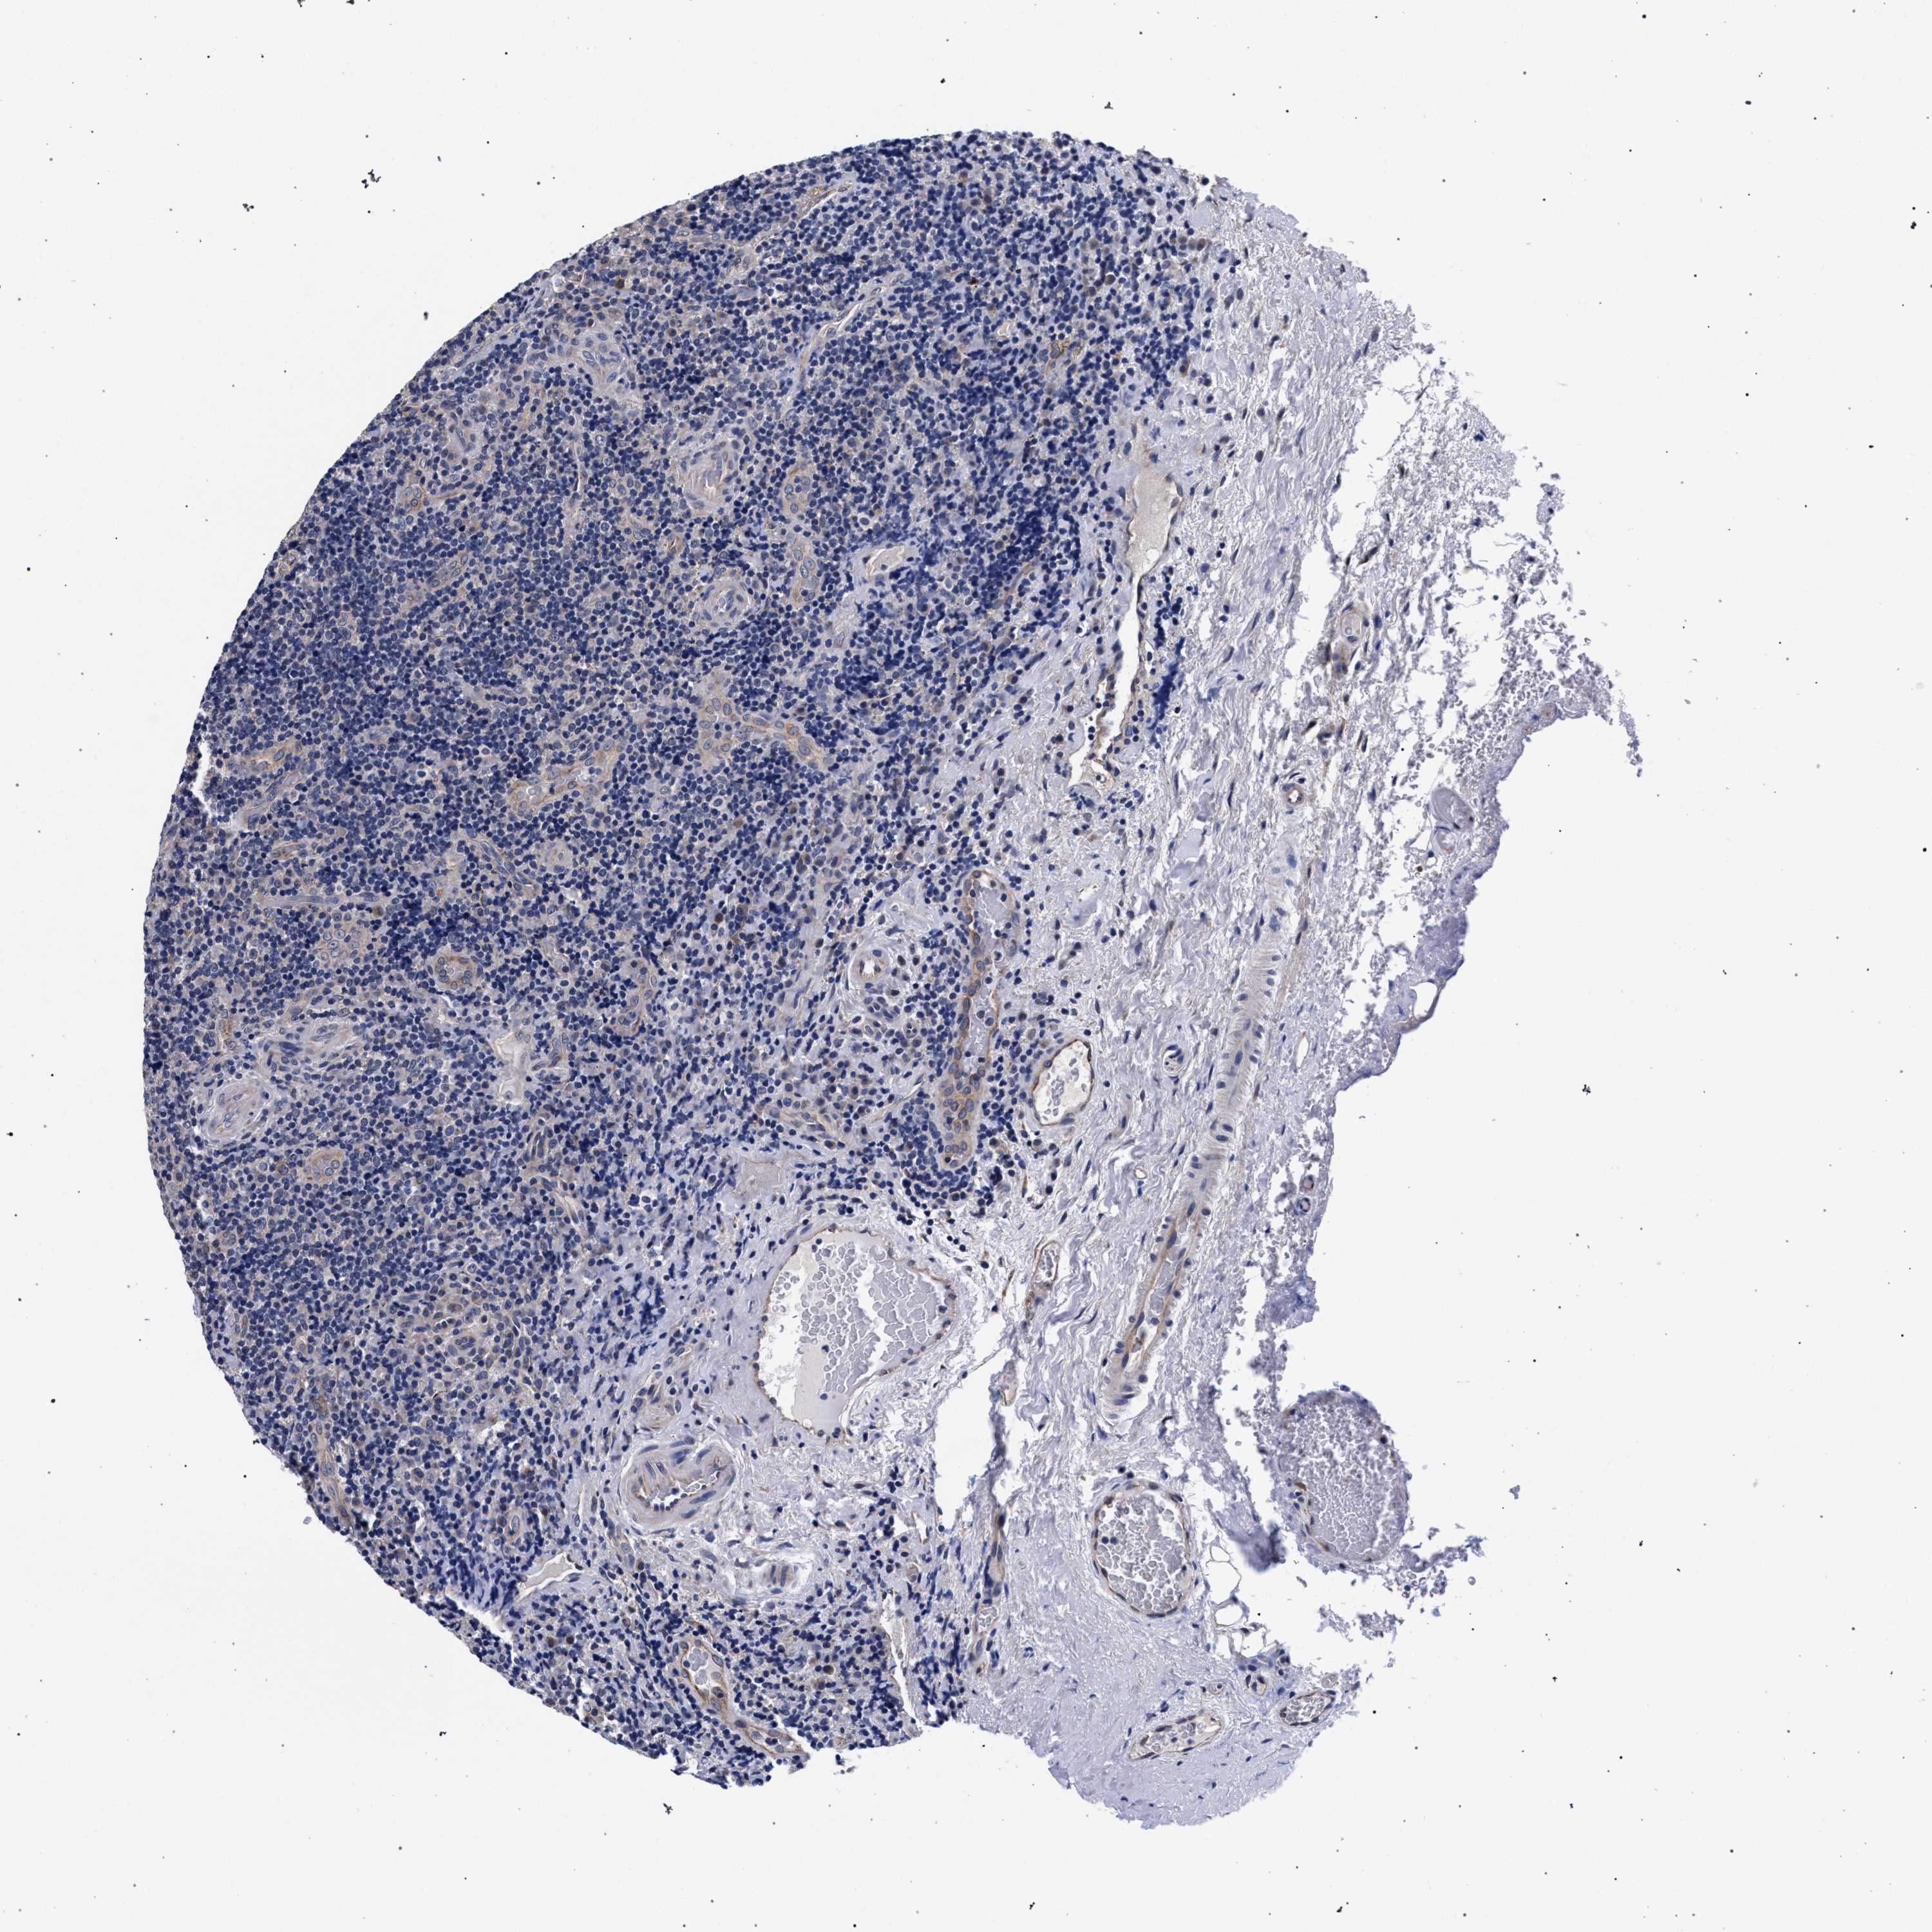

LYMPHOMA - Protein expressioni

A mouse-over function shows sample information and annotation data. Click on an image to view it in a full screen mode. Samples can be filtered based on level of antibody staining by selecting one or several of the following categories: high, medium, low and not detected. The assay and annotation is described here.

Each image is clickable and will lead to virtual microscopy that enables deeper exploration of all samples and also displays staining intensity scores, fraction scores and subcellular localization as well as patient and tissue information for each sample.

Antibody HPA021497

Hodgkin's disease, NOS

Malignant lymphoma, non-Hodgkin's type, High grade

Malignant lymphoma, non-Hodgkin's type, Low grade